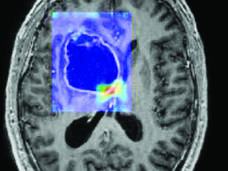

¿Sirve la inteligencia artificial para ver el cáncer de formas nuevas y más eficaces?

Los investigadores crean herramientas de inteligencia artificial (IA) que podrían obtener imágenes del cáncer más rápido, con más precisión y más información. Pero también hay inquietudes sobre si estas técnicas están listas para los consultorios médicos; si beneficiarán a las personas; y si ese beneficio llegará a todos o solo a algunos de los pacientes.